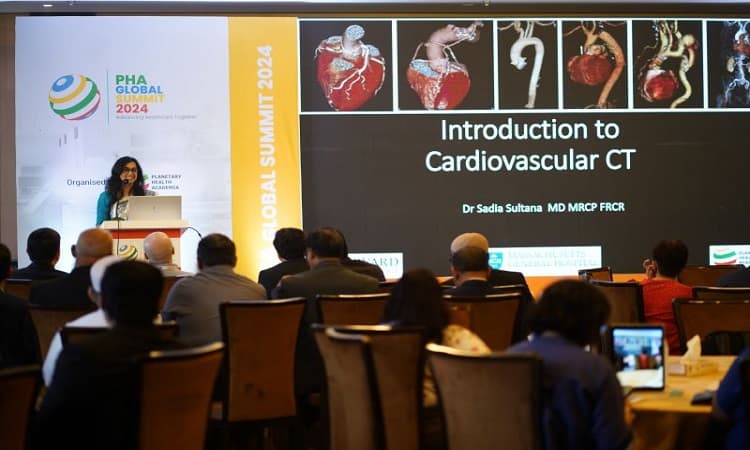

আজ ‘পিএইচএ গ্লোবাল সামিট-২০২৪’ এর উদ্বোধন

'পিএইচএ গ্লোবাল সামিট-২০২৪' উদ্বোধন করেছেন স্বাস্থ্য ও পরিবারকল্যাণ মন্ত্রী জাহিদ মালেক। এতে ২,০০০+ চিকিৎসক, গবেষক ও শিক্ষাবিদ অংশগ্রহণ করছেন। সম্মেলনে ৩০টির বেশি কোর্স ও বৈজ্ঞানিক সেশন অনুষ্ঠিত হবে।

পিএইচএ গ্লোবাল সামিট: দেশে প্রথমবারের মত হচ্ছে লন্ডন কোর রিভিউ কোর্স

পিএইচএ গ্লোবাল সামিট-২০২৪ এর অংশ হিসেবে বাংলাদেশে প্রথমবারের মতো লন্ডন কোর রিভিউ কোর্স অনুষ্ঠিত হয়। ইউনাইটেড কনভেনশন সেন্টারে ১৮-২২ ফেব্রুয়ারি কার্ডিওথোরাসিক সার্জারির সাম্প্রতিক অগ্রগতি নিয়ে আন্তর্জাতিক ও জাতীয় চিকিৎসকরা অংশগ্রহণ করেন।

ঢাকায় ২৪ ও ২৫ ফেব্রুয়ারি হচ্ছে দক্ষিণ এশিয়ার বৃহৎ স্বাস্থ্য সম্মেলন

২০২৪ সালের ফেব্রুয়ারিতে ঢাকায় অনুষ্ঠিত 'পিএইচএ গ্লোবাল সামিট-২০২৪'-এ অংশ নেন ২,০০০+ চিকিৎসক ও গবেষক। ২৪–২৫ ফেব্রুয়ারি অনুষ্ঠিত মূল পর্বে ৫০ আন্তর্জাতিক বক্তা ও ৩০টির বেশি কোর্স ছিল।

স্বাস্থ্য নিয়ে ঢাকায় হতে যাচ্ছে এশিয়ার সবচেয়ে বড় সম্মেলন2024

‘পিএইচএ গ্লোবাল সামিট-২০২৪’ ঢাকায় প্রথমবার আয়োজিত হয় ফেব্রুয়ারিতে। ৯ দিনব্যাপী এই সম্মেলনে ২০০০+ চিকিৎসক, ৫০ আন্তর্জাতিক বক্তা ও ১০০ দেশি বিশেষজ্ঞ অংশ নেন। আয়োজনে ছিল ৩০+ বৈজ্ঞানিক সেশন ও ক্যারিয়ার গাইডেন্স।